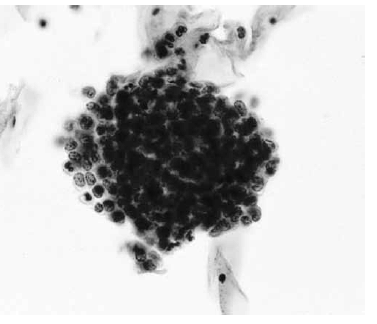

Nas questões de números 46 a 60, assinale a alternativa que melhor corresponde ao diagnóstico do quadro microscópico apresentado.

Células endometriais.